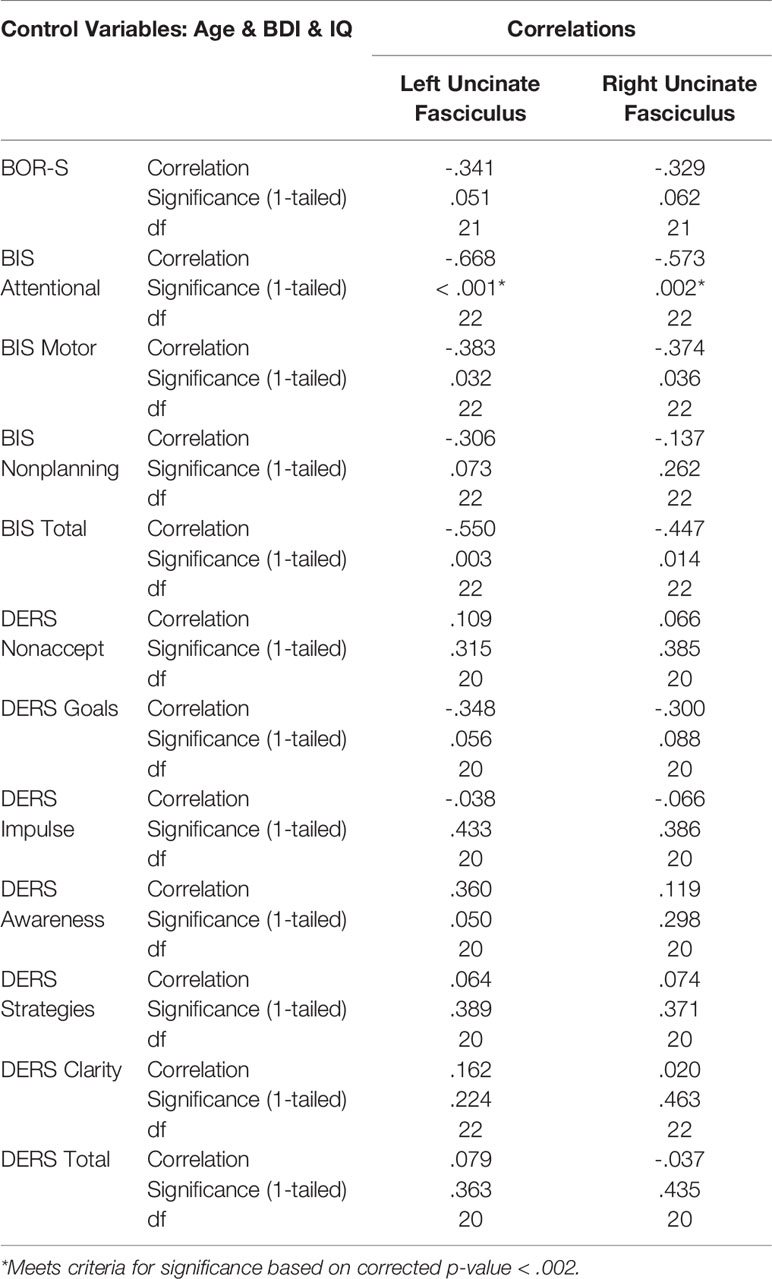

Within the NSSI group, we conducted correlations between GFA and clinical measures using partial Pearson’s correlations controlling for age and IQ. To allow our analyses to be more specific to NSSI, as opposed to depressive symptoms, we included BDI scores as covariates. We performed correlations between GFA of the right and left uncinate fasciculus and scores from the 7 DERS scales, 4 BIS scales, and the BOR-S scale from the PAI/PAI-A. Given the total of 24 comparisons and our hypothesis that higher scores on these clinical measures will be associated with lower GFA values, we used a one-tailed p-value < .002 as our level of significance. We used the same method for the right and left cingulum including using a one-tailed p-value < .002. We elected to use one-tailed p-values due to our a priori hypotheses that higher scores on clinical measures will correspond to lower GFA values.

Lower GFA of the left and right uncinate fasciculus was associated with higher total scores on the attentional subscale of the BIS. A correlation matrix can be found in Table 2, which includes comparisons that were significant at an uncorrected p < .05. For the left and right cingulum, there were no significant associations with measures of self-regulation (DERS and BIS). A correlation matrix can be found in Table 3. Finally, lower GFA of the left cingulum was associated with a longer duration of NSSI. There were no significant correlations between other severity indices (e.g., average number of episodes) and GFA. These in addition to results from other comparisons can be found in the correlation matrix in Table 4.

We also examined the association between clinical measures and GFA within the NSSI group while controlling for age, IQ, and BDI-II scores. Lower GFA within the uncinate fasciculus, which serves brain regions implicated in self-regulation, was significantly associated with higher scores on the attentional subscale of the BIS. Given the role the uncinate fasciculus plays in serving as a connection between subcortical structures and frontal regulatory regions, the present findings suggest that those who experience racing and intrusive thoughts or difficulties with focusing on tasks may show compromised white matter organization within this tract. Decreased FA in the uncinate fasciculus has been associated with BPD (40, 41), emotion dysregulation disorders (42), and suicide attempts (43–46). While the relationship between NSSI and impulsivity remains controversial, a recent review provides helpful insight regarding the complexities of this relationship. Lockwood and colleagues (17) highlight that mood-dependent impulsivity, such as that measured by Negative Urgency in the UPPS Impulsive Behavior Scale (47), predisposes an individual to begin engaging in NSSI; while higher scores on more cognitively-related facets of impulsivity were more reflective of recent NSSI, and thus may serve to maintain the behavior. This is consistent with the relationship between BIS scores and GFA within our sample of NSSI participants as they had been engaging in recent self-injury. However, it is necessary to further elaborate on these relationships by also incorporating measures investigating mood-dependent impulsivity.